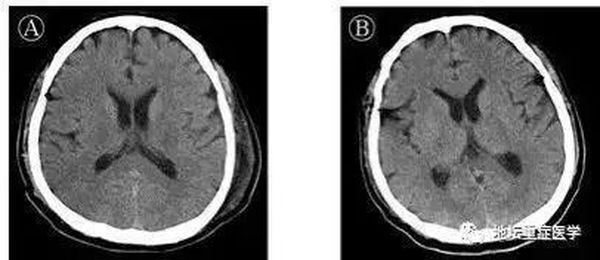

许先生1月24日以新冠肺炎、危重型、呼吸衰竭收入院。入院后给予联合干扰素雾化、抗病毒治疗,预防细菌感染,并给予中医辨证用药。未见好转,高热,乏力,呼吸困难逐渐加重。1月27日(起病第10天)胸部CT显示双肺磨玻璃密度影范围扩大,部分实变影。短暂予经鼻高流量吸氧,其呼吸窘迫无缓解,烦躁不安,呼吸50次/分,氧分压85%,在ICU进行气管插管,按照重度呼吸窘迫综合征(ARDS)的呼吸通气原则进行机械通气。治疗96小时后(起病第14天),患者出现颌面及口角频繁抽搐,伴持续呃逆,医生查体发现颈抵抗阳性,双侧瞳孔等大等圆,对光反射迟钝,四肢肌张力升高,双侧膝反射亢进,双侧巴氏征及踝阵挛阳性,头颅CT颅内未见异常,测脑脊液压力大于330mmH2O,脑脊液外观无色清亮,生化检测无异常。北京地坛医院重症医学科、检验科及中国疾控中心传染病所联合工作组对采集的脑脊液标本进行宏基因组二代测序、鉴定可能的感染病原体过程中,排除了其他病原体,获得了SARS-CoV-2病毒基因组序列。通过基因测序证实脑脊液中存在SARS-CoV-2,临床诊断病毒性脑炎。

医护人员经过对其14天机械通气和甘露醇控制颅压、咪唑安定控制抽搐、丙种球蛋白及甲基强的松龙抗炎等针对病毒性脑炎的处理,观察患者肺病影像学逐渐好转,神经系统症状消失。